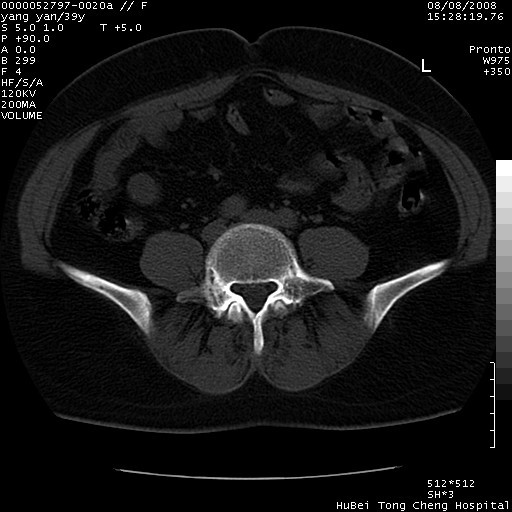

患者 女,39岁。因外伤检查,偶然发现。

典型!双侧骶髂关节致密性骨炎。

典型!病变主要累及双侧髂骨。常见于育龄期妇女。

致密性骨炎,一般不跨越关节面,可是这个骶骨关节面也有硬化。

髂骨致密性骨炎系一种以骨质硬化为特点的非特异性炎症,有高度致密的骨硬化现象,尤其以髂骨下2/3更为明显,但关节间隙则无改变。因位于骶髂关节,且该关节症状明显,故又称之为“骶髂关节致密性骨炎”。 本病90%以上为中年女性,以妊娠后期、尤其分娩后为多见,亦可见于尿路或女性附件慢性感染后,或盆腔内其他感染。此外,臀骶部的外伤亦可诱发或引起本病。  妊娠、分娩及外伤均可引起骶髂关节韧带的撕裂而易使局部的血供受阻。因此早期局部呈现充血、水肿及渗出增加等,渐而局部出现增生与变性反应,随着胶原纤维的致密化而向硬化演变;血管形成厚壁血管,易闭塞而引起髂骨耳状面处缺血和缺氧,骨质呈现硬化性改变,以致手术时局部出血较少。骶髂关节囊壁显示纤维增生、弹性降低及松动样改变。继发于盆腔内炎症者亦出现相类似的病理改变,可能系细菌内毒素作用所致。